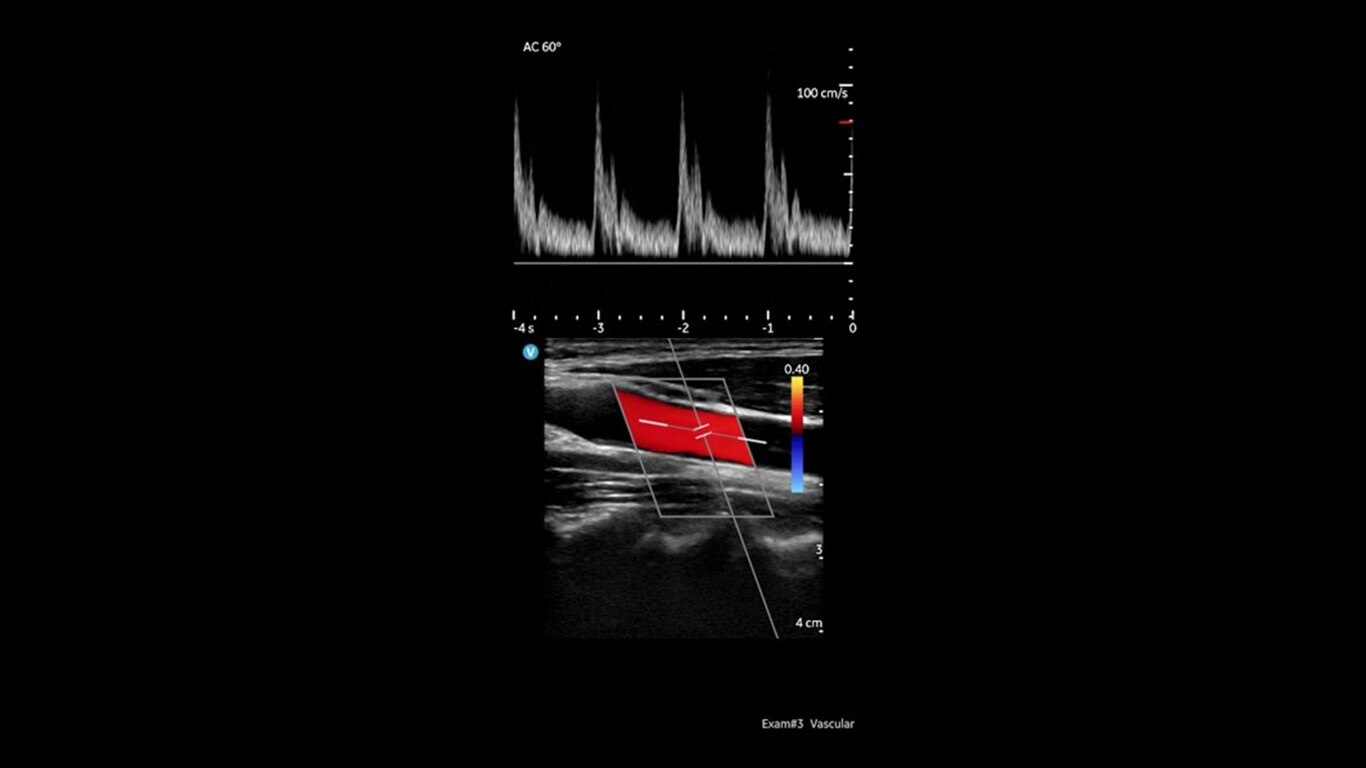

Vscan Air SL offers sector and linear transducers in a dual-probe configuration. Its sector transducer is ideal for rapid cardiac assessments. The opposite side of the probe has a linear array, so you won’t miss a beat when moving from a cardiac to a vascular assessment.

Linear array: Peripheral Vascular, Lung/Thoracic (Adult /Pediatric), Small organs (Adult/Pediatric), Musculoskeletal — (Superficial and conventional) (Adult/Pediatrics), Nerves (Adult/Pediatrics), Neck and airway (Adult /Pediatric), Procedural guidance (Adult/Pediatrics), Ophthalmic*, Cephalic (Neonatal).